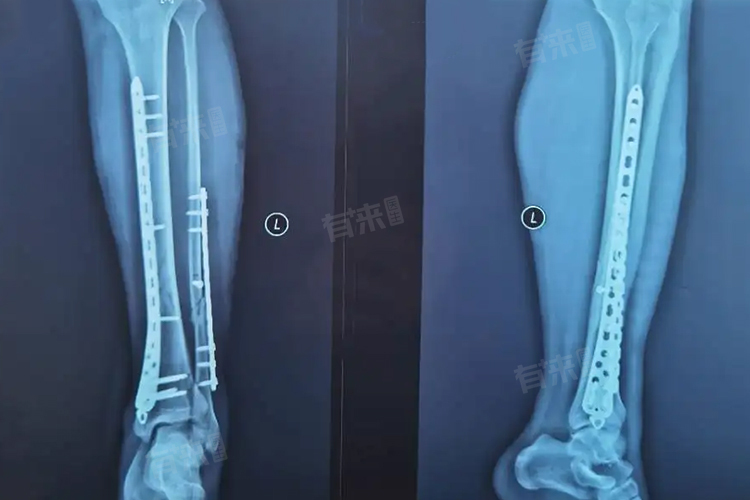

- 术前检查:术前需要进行一系列的检查,以确保患者身体状况适合手术。常规的检查包括血常规、凝血功能、传染病四项、心电图、X光片或者CT等。检查的费用大概在500-1500元,例如血常规检查一般在几十元,而CT检查可能在300-800元,具体费用取决于检查的部位和设备的先进程度。

- 术后复查:术后也需要进行复查,主要是查看伤口愈合情况以及是否有其他并发症。复查项目可能包括X光片等,费用大概在100-300元。